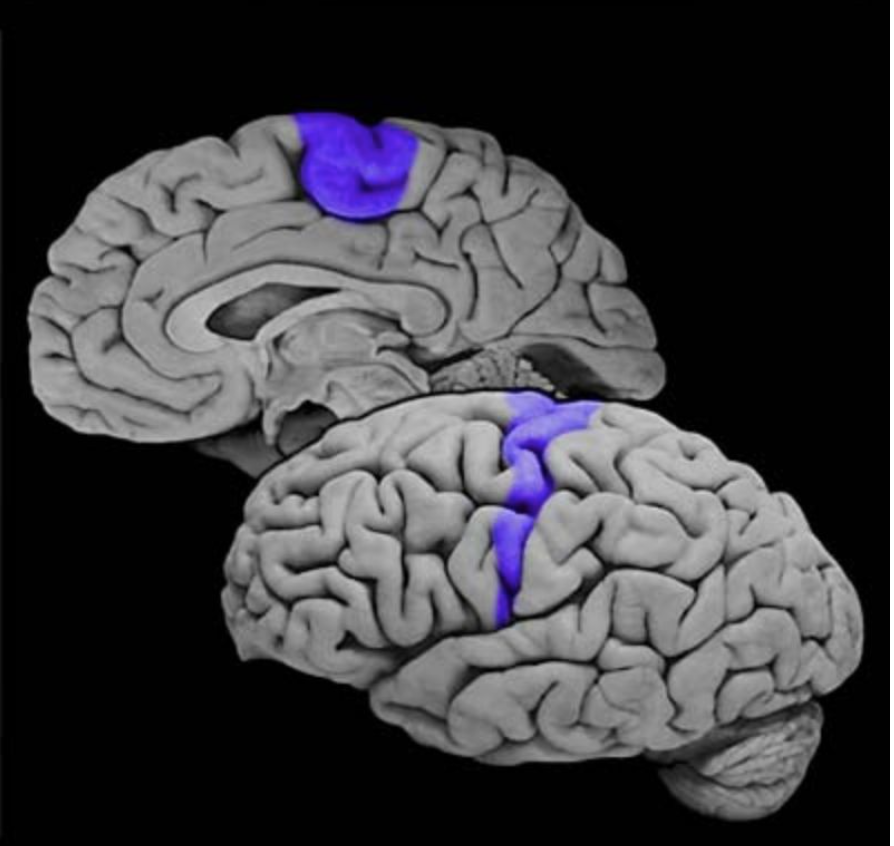

Postcentral gyrus

Vertically oriented gyrus that forms the posterior bank of the central sulcus; this gyrus contains the primary somatosensory cortex.

Primary somatic sensory cortex

Cortical areas (Brodmann's areas 3, 1 and 2) in the postcentral gyrus that first receive somatosensory signals from the relevant thalamic nuclei (ventral posterior complex). Also called primary “somatosensory” cortex.

Brodmann's Area 1

Sensory cortical area in the crest of the postcentral gyrus; this area is a component of the primary somatosensory cortex.

Brodmann's Area 2

Sensory cortical area in the crest and posterior bank of the postcentral gyrus; this area is a component of the primary somatosensory cortex.

Brodmann's Area 3

Sensory cortical area in the posterior bank of the central sulcus (postcentral gyrus); this area is a principal component of the primary somatosensory cortex. Area 3 is further subdivided into area 3a, which receives proprioceptive signals that originate in deep receptors, and area 3b, which receives discriminitive mechanosensory signals that arise from cutaneous receptors.